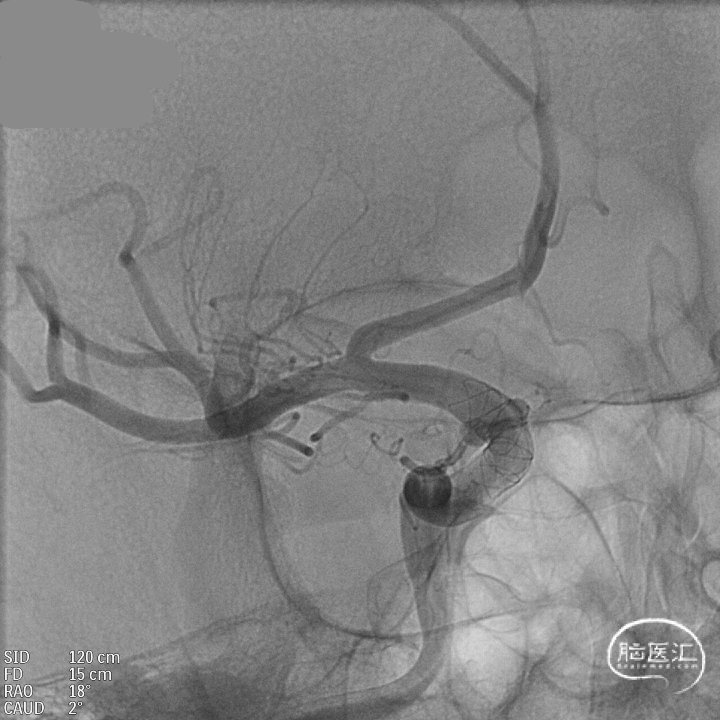

DSA:DSA提示右侧大脑中动脉M1段动脉瘤,左侧大脑前动脉A1段发育不良。

其他血管造影未见明显异常。

术前诊断:动脉瘤位于M1主干,考虑夹层动脉瘤可能大。

载瘤动脉远端血管直径:2.4mm

载瘤动脉近端血管直径:2.5mm

动脉瘤尺寸:(瘤颈口宽度2.0mm/瘤体高度1.86mm/瘤囊宽度1.85mm)

手术方案:血流导向装置植入术。

密网支架:强易达Choydar血流导向装置 FD250-15

微导管到位:Synchro微导丝引领支架微导管通过病变血管进入大脑中动脉M2段。

支架到位,原位释放,前段打开。

造影确认支架远端打开充分,贴壁良好,继续推送支架。

支架全部释放,调整张力,微导管通过支架,回收输送导丝。

支架内使用成襻微导丝进行按摩,使支架充分贴壁。

术后造影:支架充分覆盖动脉瘤瘤颈,贴壁良好,瘤体内可见造影剂滞留。

术后支架显影:定位精准,未覆盖颞前动脉及大脑前动脉。